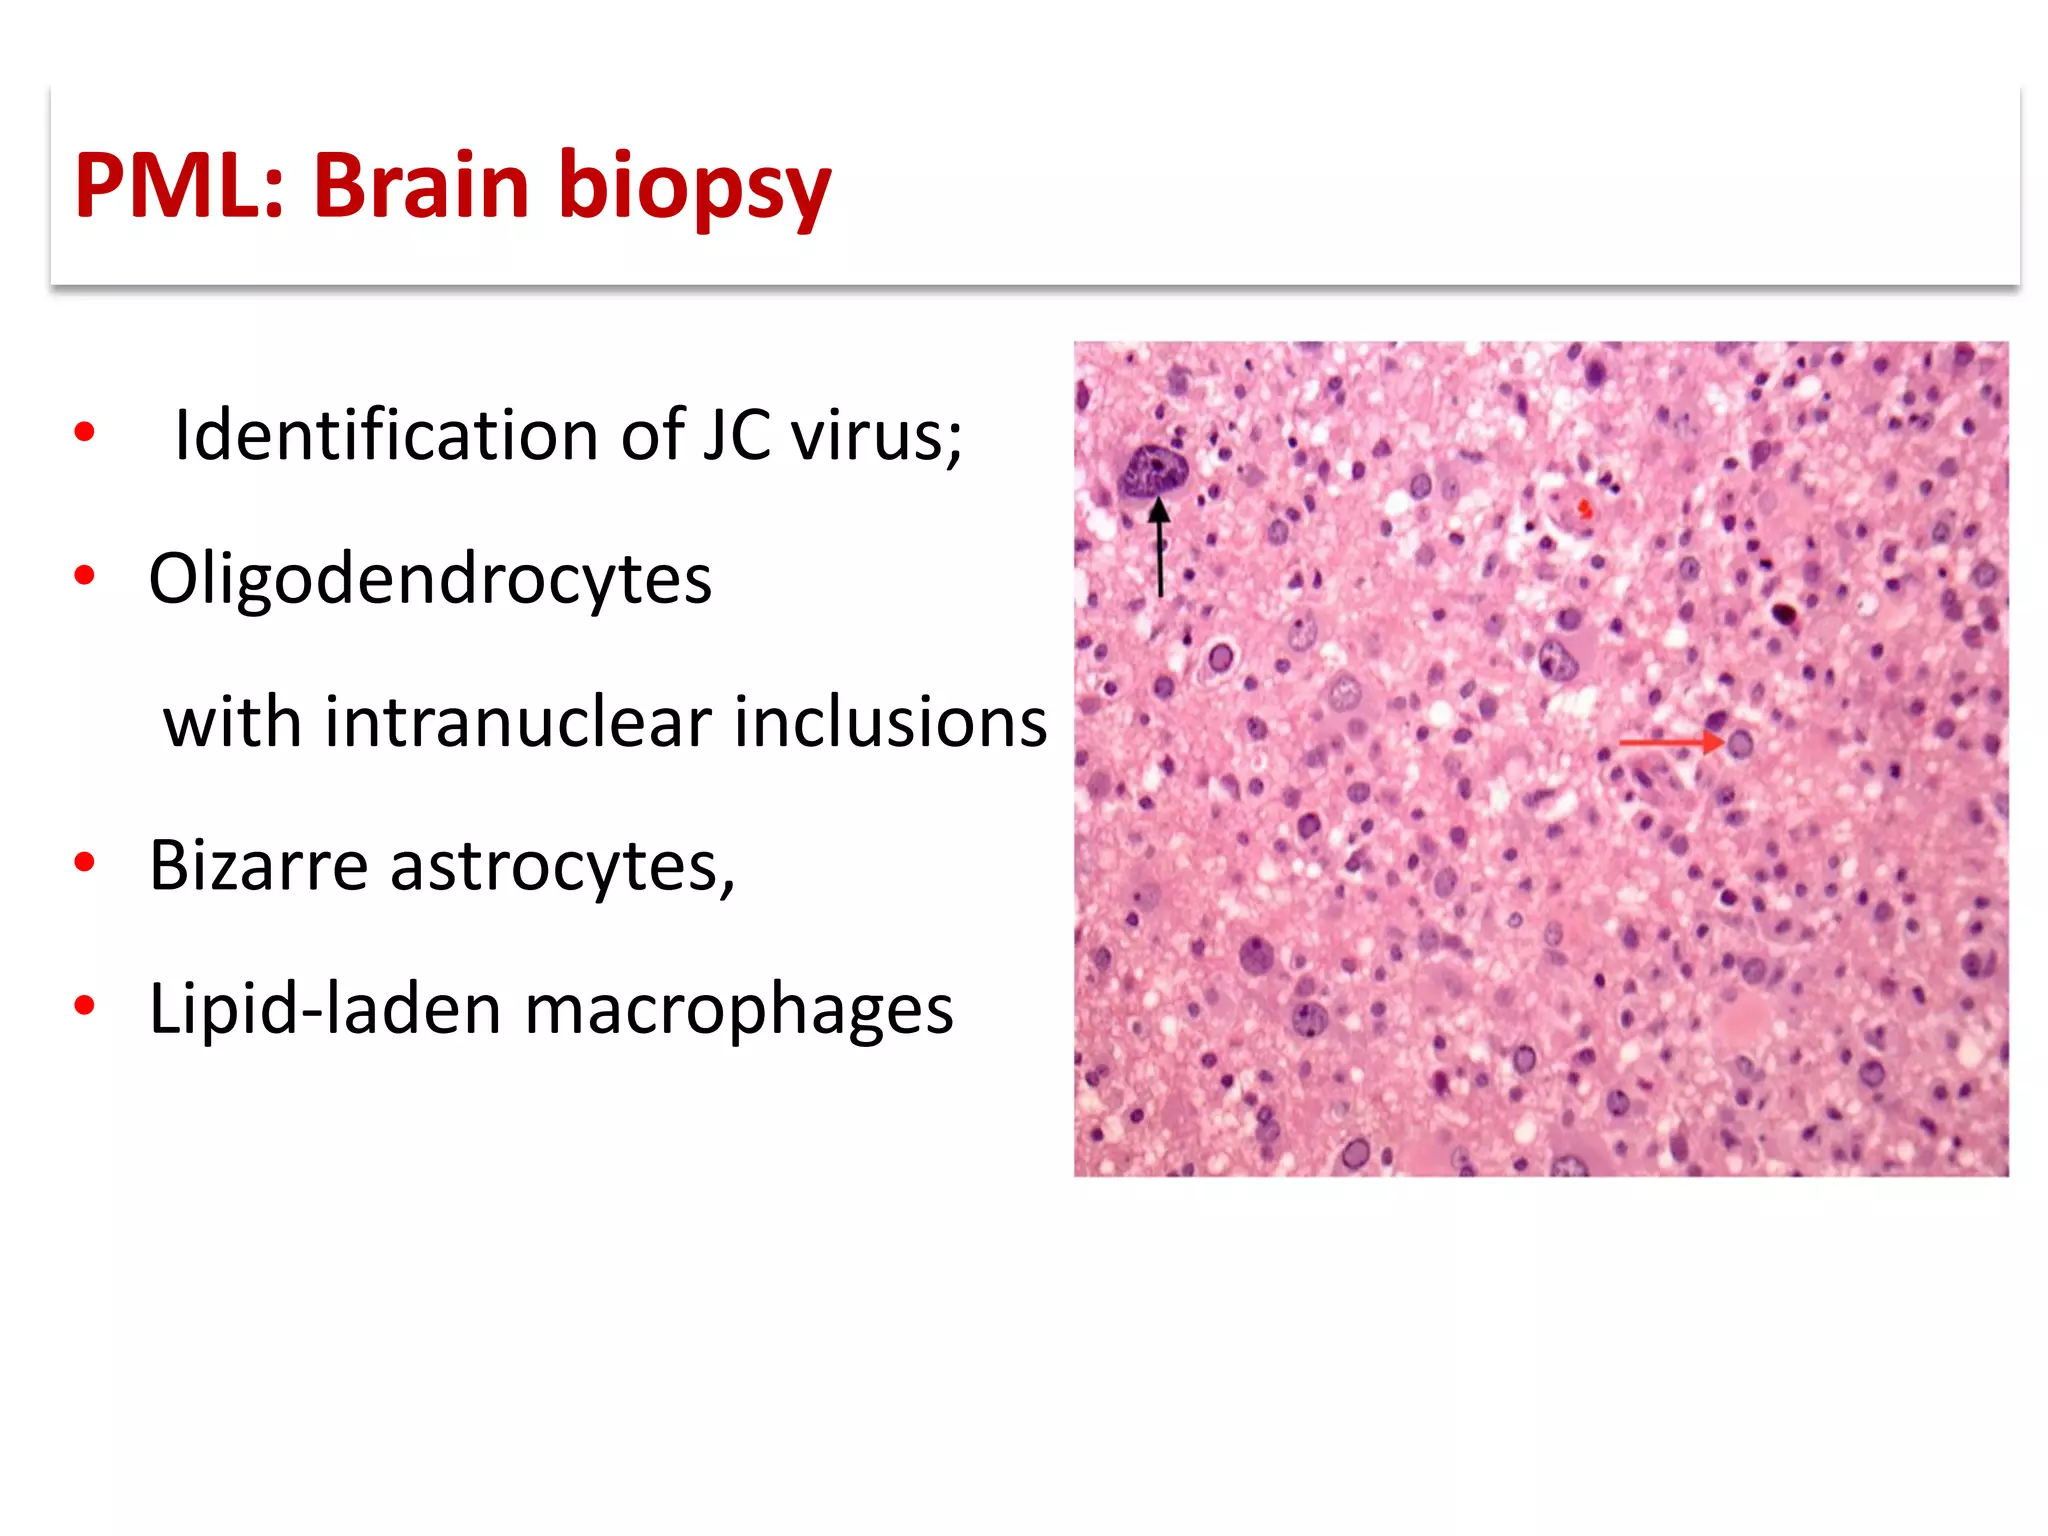

This document discusses progressive multifocal leukoencephalopathy (PML), an opportunistic infection caused by the John Cunningham virus (JCV) that leads to demyelination in the central nervous system. It highlights the epidemiology, clinical manifestations, diagnostic methods, and risk factors associated with PML, particularly in immunocompromised patients and those undergoing immunomodulatory therapies. It also presents data on the incidence of PML in patients treated with natalizumab and other therapies, addressing the relationships between these treatments and the development of PML.